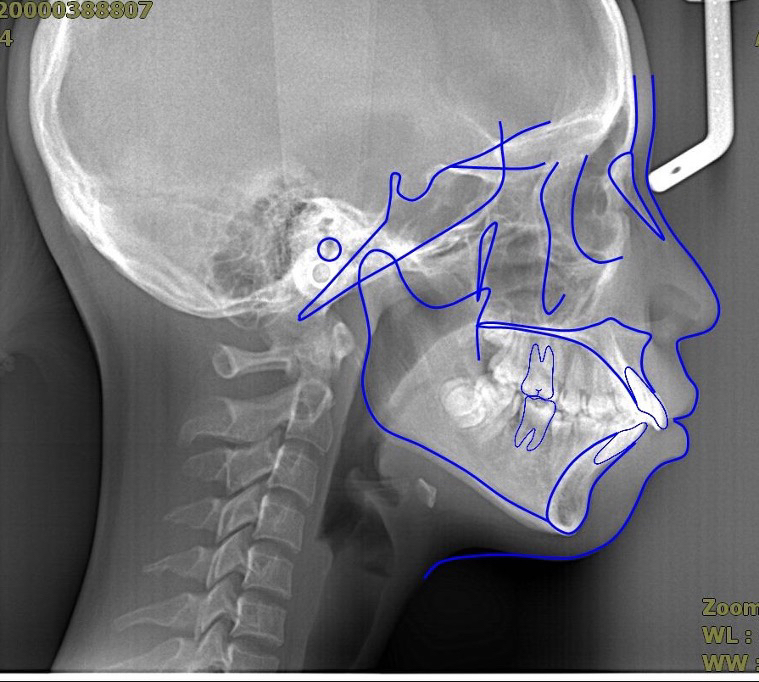

我们借助头颅侧位片进行头影测量分析(图2),可以分析上颌骨、下颌骨、牙齿、软组织的情况,这是所有专业正畸医生需要掌握的技能,有利于做出正确的矫正方案。同时,在结束矫正的时候对矫正前后进行头影测量分析(图3),可以分析矫正效果,知其然知其所以然。